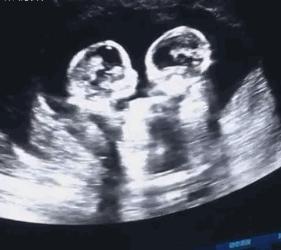

闺蜜怀了一对双胞胎,她很好奇双胞胎在子宫里是怎样相处的,会不会打架,脐带会不会缠绕?今天就跟大家科普一下双胎在子宫内是怎样相处的。

3、单绒毛膜单羊膜囊单卵双胎 分裂发生在9-13日,两个胎儿共同存在于一个羊膜腔内,拥有同一个胎盘。这样同一个根上的小树中间没有任何隔膜,难免会发生磕磕碰碰。不过他们平时都很文静,一般不会发生大动作。